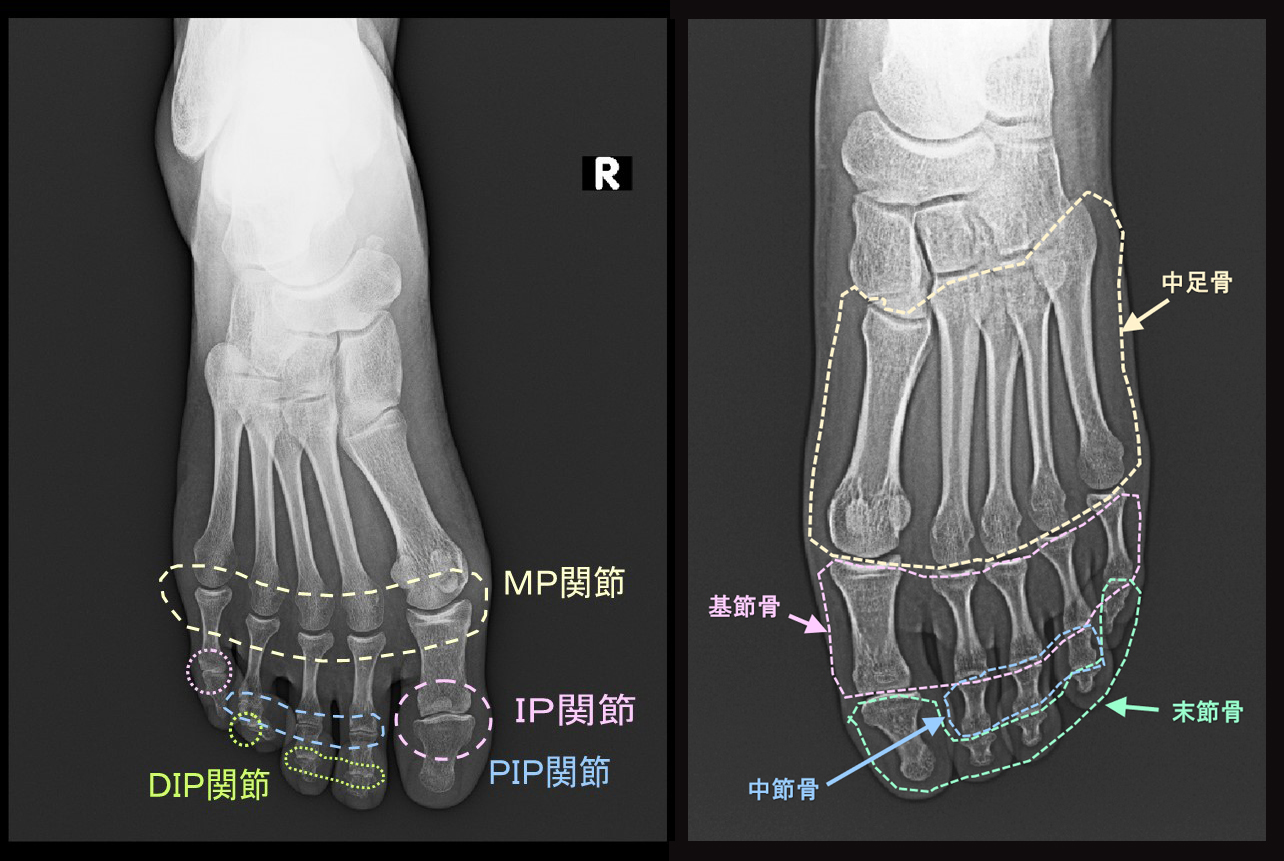

まず、スポーツ愛好者の記事同様に足部の構造を提示します。中足骨という骨の名前とMP関節という名称だけは記憶してください。

足の骨格.jpg